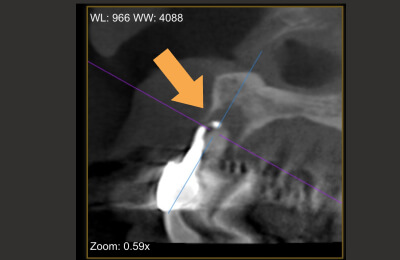

術前

矢印部に大きな骨吸収像

-

治療中

根管を清掃した後

術後

骨の再生が見られる

| 主訴 | 噛むと違和感がある。 レントゲンで根の先に黒い影を指摘された。 |

|---|---|

| 治療期間 | 根管治療3回 補綴治療3回 |

| 治療費 |

(ファイバーコア・ジルコニアクラウン) |

| 治療内容 |

通法の根管治療を行いました。ラバーダム防湿、 マイクロスコープ下で未処置であった根管を発見し処置。 |

| 治療のリスク |

治療直後は反応性に一時的な腫れや痛みが出る可能性があります。 根管治療で改善が見られない場合は外科的根管治療が必要になる場合があります。 |